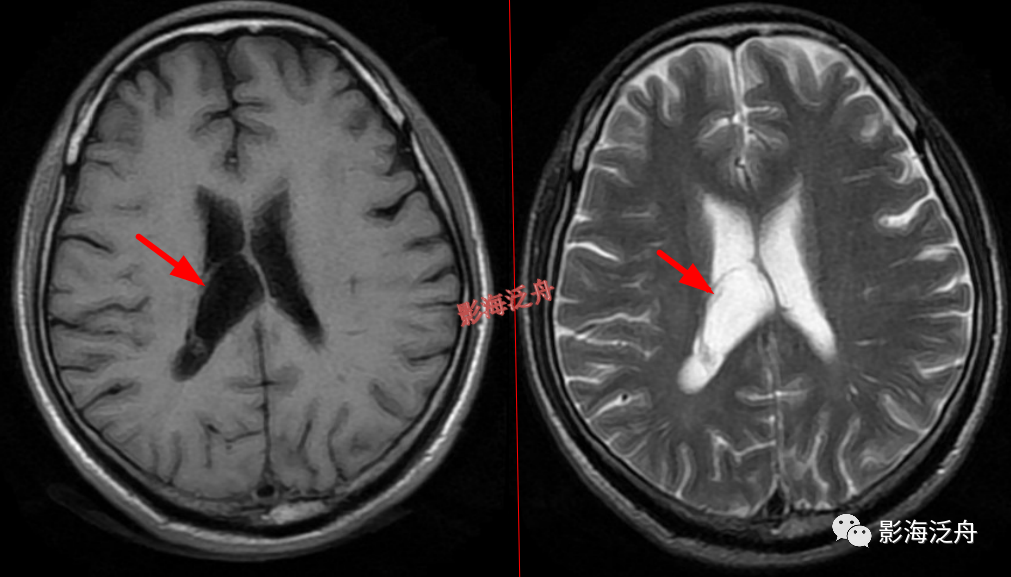

透明隔缺如,我自己漏诊过的病例。上面有很多正常的图像可供对比观察。